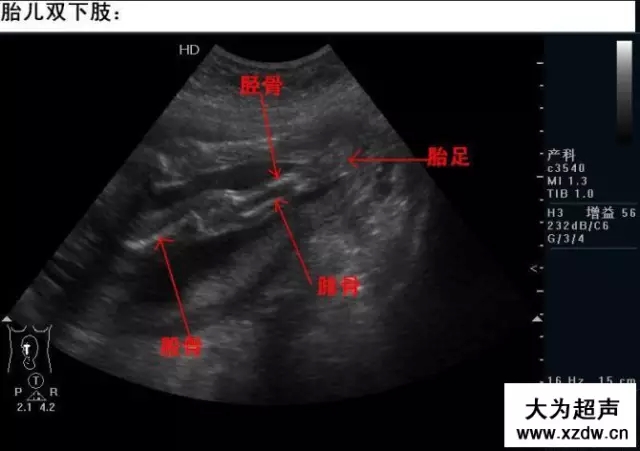

產科超聲正常圖片